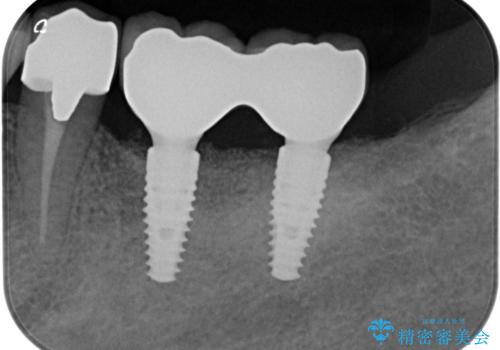

抜歯後、インプラントを用いて咬合機能を回復すると共に周囲に強固な角化歯肉を移植することによりより長期にわたり安定したインプラント周囲環境となるよう治療を計画します。

- 83.6万円(インプラント×2・アバットメント×2・クラウン×2)費用は治療当時の料金となります

インプラント周囲の角化歯肉が存在することにより、歯ブラシがしやすくなりインプラントにトラブルが起きる確率を減らしより長期的な予後を望むことができます。